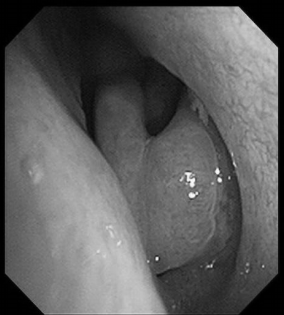

电子喉镜检查:鼻息肉(双)